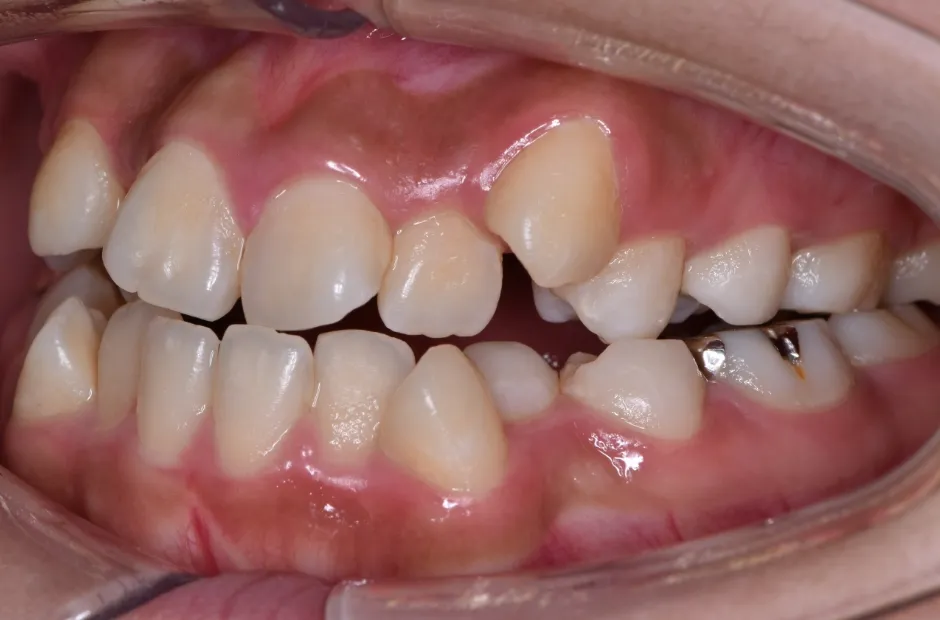

治療症例

ブラケット矯正

前歯部反対咬合

| 診断名・主訴 | 前歯部反対咬合 |

|---|---|

| 年齢・性別 | 14歳・男性 |

| 治療期間・回数 | 1年2か月 |

| 治療に用いた主な装置 | ブラケット矯正 |

| 抜歯部位 | なし |

| 治療費 | 60万円(税抜) |

| リスク・副作用 | 装置による違和感・疼痛・歯肉退縮・歯根吸収・虫歯のリスクなど |

治療前

治療中

治療後